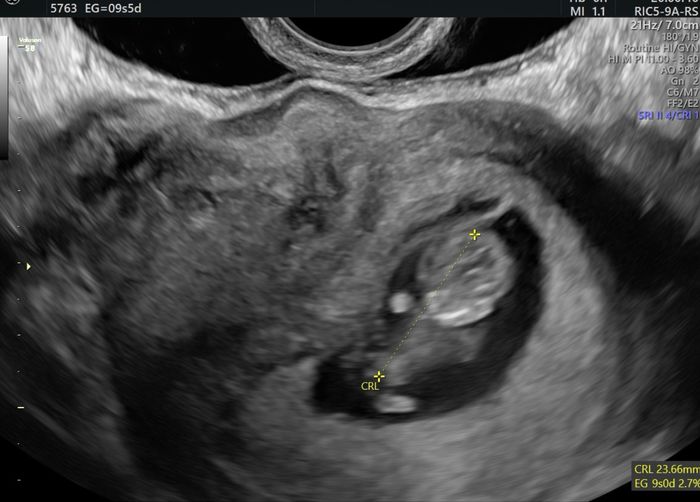

Hola! A ver si por la eco sabéis qué puede ser. Es una eco transvaginal de 9+2. Está del revés porque me dijo que estaba con la cabeza hacia abajo. Graciaas!Método Ramzi 8